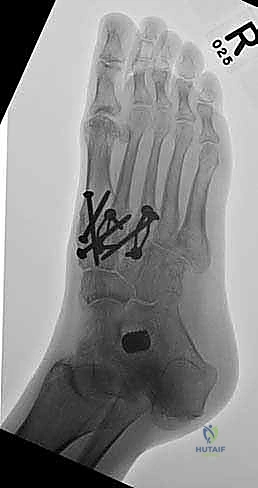

6. التثبيت الصلب (Rigid Fixation)

لضمان التحام العظام لتصبح عظمة واحدة صلبة، يجب تثبيتها بقوة هائلة حتى لا تتحرك أثناء فترة الشفاء. يتم استخدام مسامير معدنية متطورة (Screws)، أو شرائح معدنية خاصة (Plates)، أو دبابيس طبية متخصصة (Staples) مصنوعة من التيتانيوم الآمن على الجسم.

بعد التأكد التام من وضع العظام وثباتها باستخدام جهاز الأشعة السينية داخل غرفة العمليات (C-Arm)، يتم إغلاق الشقوق الج